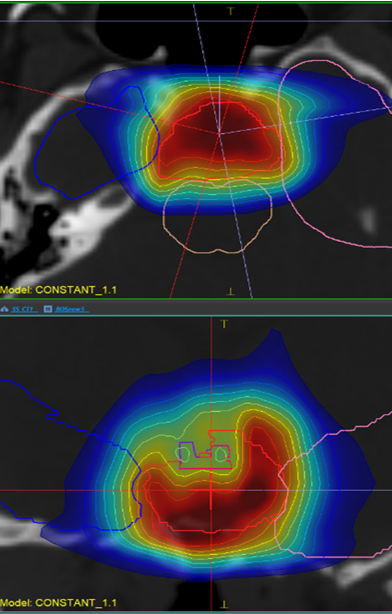

The comparative planning workshop featured an extremely complex case. The four participating centres each created comparative proton-photon treatment plans. The CTV was abutting critical organs at risk such as optic chiasm, optic nerves, brainstem and hippocampi. In addition to this, the requirement for a high prescription dose meant that significant optimization trade-offs were required.

The Australian Bragg Centre team utilized MonacoPT to generate the proton therapy treatment plan and used unique features including constrained optimization, dynamic spot placements and Linear Energy Transfer (LET) analysis. The robustness optimization display also allowed the team to view approximate doses during optimization, not having to navigate through multiple windows.

Dose view

LET view